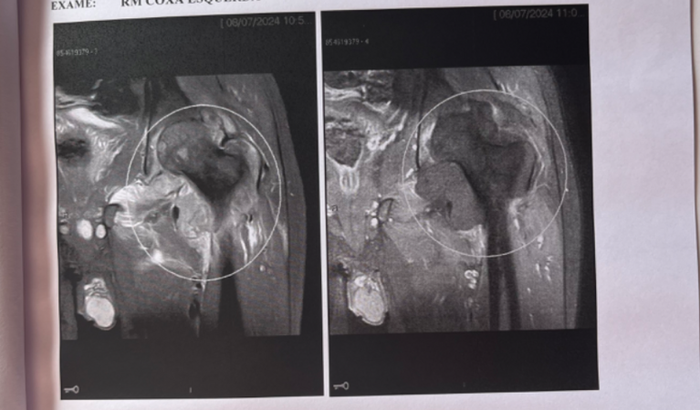

Olá me chamo Jeferson de Brito, tenho 19 anos sou natural de Picui- PB, atualmente moro com minha família em Pomerode- SC. Há mais ou menos três meses eu comecei com dores na região do joelho, seguindo para coxa, procurei atendimento médico, onde o mesmo solicitou exames de imagens RX, logo após realizei uma ultrassonografia a pedido médico, que não foi o suficiente para o diagnóstico preciso. As dores começaram a aumentar, remédios para dor não era suficiente. Por orientação procurei um especialista com ajuda de amigos e próximos, onde o mesmo de início me pediu outro exame de imagem RX, após realizado volto ao consultório, onde o mesmo imediatamente me requisitou uma ressonância magnética com urgência , fui realizar a ressonância mas a mesma não foi realizada devido a muitas dores, retorno ao médico ortopedista, onde requisitou o exame com sedação devido as minhas dores. Exame realizado o médico Ortopedista orientou que meu caso é cirúrgico, e de emergência para a retirada do tumor, onde mostra uma lesão expansiva / infiltrativa centrada na articulação coxofemoral . Com um provável SARCOMA SINOVIAL. Estou no aguardo da consulta com um Oncologista, e venho aqui através dessa vaquinha pedir o apoio de todos que se solidarizar com minha causa com qualquer valor que poder ser doado de coração, para custear, em medicação, locomoção e exames futuros. Que Deus abençoe a todos !